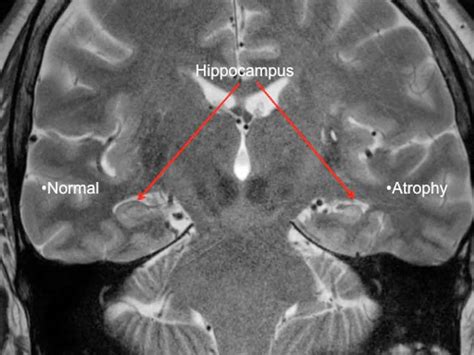

• Hippocampal Sclerosis: This is the most common cause, involving scarring or shrinkage of the hippocampus.

• MRI (Magnetic Resonance Imaging): Provides high-resolution images to check for structural issues like tumors or scarring.